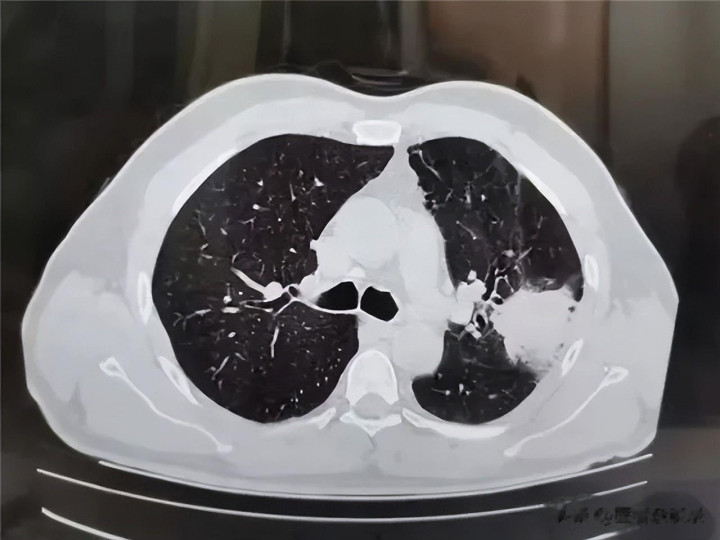

当先,低剂量螺旋 CT(LDCT)是性价比最优的筛查之选,它作为当下海外公认的肺癌筛查金措施,在肺癌筛查范围具有不可替代的地位。与平素 CT 比拟,它的辐照量裁减约 70%-80%,仅等同于几十张胸片的辐照剂量。低辐照赋予其高度安全性,符合每年作为体检技俩开展一次。

它能判辨地自大结节的大小、密度和格式,是发现和处分肺结节的基础,如果你仅仅旧例体检发现微小结节,遵医嘱如期作念这个检查就够了,既经济又宽解。

其次,当 CT 发现结节格式可疑,需要进一步看清细节时,大夫可能会漠视作念高辨别率 CT(HRCT)或薄层 CT。这项检查能把扫描层厚压缩到 1 毫米致使更薄,就像给结节律了“超清特写”,能了了地看到结节里面有莫得空泡,血管是否穿过,旯旮是否有毛刺等轻飘结构。这关于判断结节的良恶性具有极高的参考价值,况且相同属于影像学检查,无创且快速。